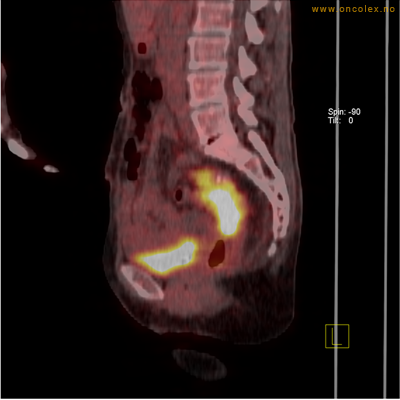

Adenokarsinom distalt i spiserør. Fysiologisk opptak i hjertemuskulatur.

Adenokarsinom langt nede i spiserøret.

Høyt opptak av 18F-FDG i adenokarsinom i rektosigmoideumovergangen. Fysiologisk opptak i blæren.